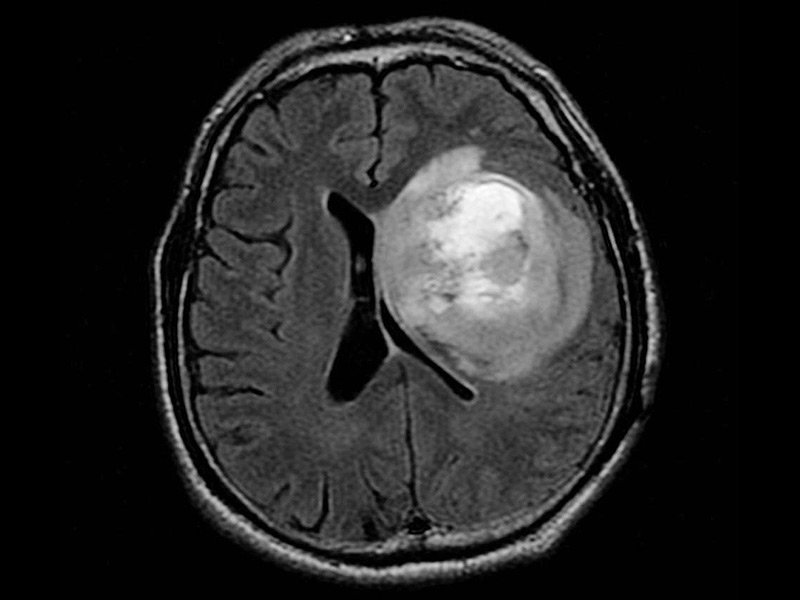

神经胶质瘤是在中枢神经系统的神经胶质细胞中形成的脑癌或脑肿瘤。胶质细胞是围绕并支持神经细胞的那些。一些脑癌起源于身体其他部位,而神经胶质瘤则起源于中枢神经系统,通常被称为“原发性”脑瘤。脑胶质瘤的治疗方法有哪些?相关阅读:8岁女孩5cm较大基底节区脑瘤成功切除记。

除了其起源的位置以外,神经胶质瘤还具有许多特征。恶性神经胶质瘤的一个重要特征是它们没有清晰可辨的界限或“弥漫性”。即使被去除,部分神经胶质瘤也经常残留并导致复发。虽然神经胶质瘤不会扩散到中枢神经系统之外,但在疾病的复发阶段,通常会在整个脑干中发现多个神经胶质瘤。

脑胶质瘤的外科手术,主要以减少肿瘤细胞数量,减少肿瘤负荷,减轻颅腔压力,减除神经功能缺失为目的。目前的胶质瘤手术,已经进入了一个微创时代,与前相比,更为顺利,创伤更为小,肿瘤切除更为完全。显微镜应用于脑胶质瘤的切除,可以更加清晰地辨别肿瘤与脑组织的边界,以及周围重要的神经血管等结构,从而能够在顺利的情况下,较大化地切除胶质瘤。神经导航的应用,将胶质瘤的手术切除,提高到新的高度。神经导航与汽车导航相类似,可以使外科医生在手术前从切口的设计、术中功能脑区的辨认以及手术切除方式的选择等方面,更加精确和细化。